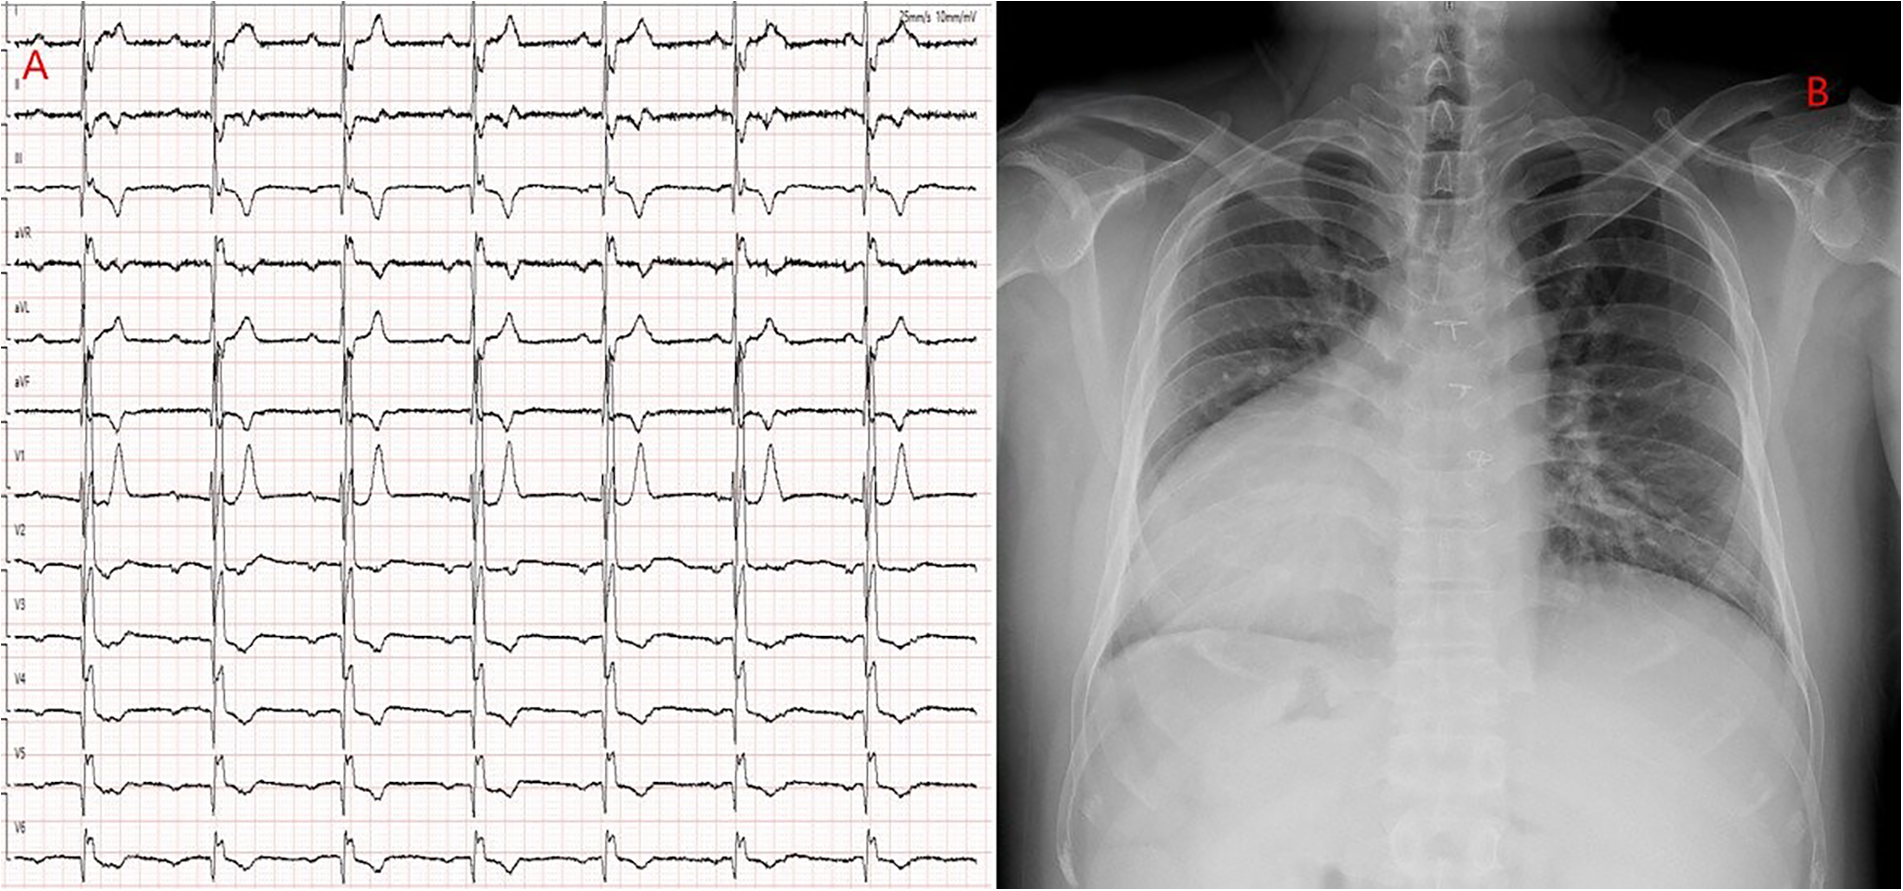

Echocardiography revealed mirror-image dextrocardia, a post-VSD repair status, and no evidence of ventricular-level shunting. Electrocardiography (performed with left and right hand electrodes reversed) demonstrated sinus rhythm, third-degree AVB, junctional escape rhythm, and complete right bundle branch block (Figure 1A). Chest radiography confirmed mirror-image dextrocardia (Figure 1B). CTA of the great vessels showed that the IVC was located on the left side of the aorta, with absence of its hepatic segment. The IVC ascended and connected to the right superior vena cava via a dilated azygos vein. The suprarenal portion of the IVC exhibited luminal stenosis, with the narrowest diameter measuring approximately 8.5 mm, while the hepatic veins drained directly into the right atrium (Figure 2). The patient fulfilled the Class I indication for pacemaker implantation (6). However, he declined a conventional lead-based pacing system and instead opted for leadless pacemaker implantation.

Figure 1

(A) ECG with reversed limb leads: Shows third-degree atrioventricular block and complete right bundle branch block. (B) Chest x-ray: Demonstrates a mirrored right-sided heart.